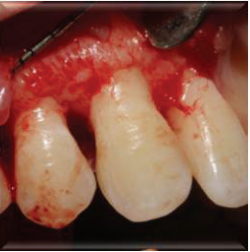

计划切除增生牙龈。由于增生范围较大,拟利用腭侧牙龈进行软组织修复。

患者1月、6月、12月后复诊,恢复良好,无复发。 牙龈纤维瘤在临床属于较常见疾病,多采用手术切除方式,注意要与其他类型牙龈增生相鉴别。手术切除纤维瘤后,若缺损较大,尤其实在美学区,影响美观,可以利用周围皮瓣进行修复。术后菌斑控制也很重要。